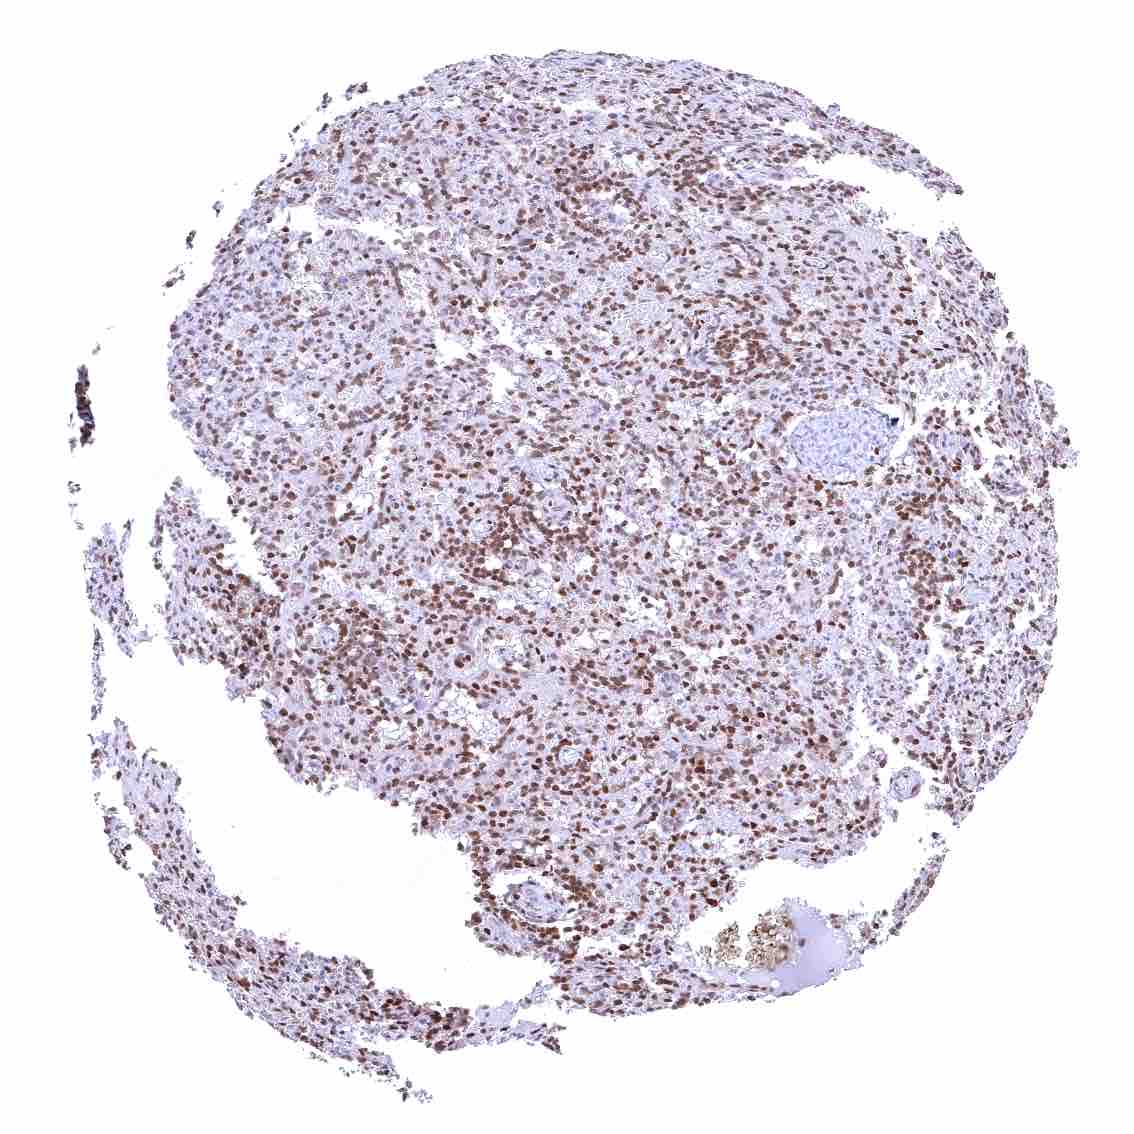

Lymph node – Strong nuclear p27 staining of a significant subset of cells, especially in the interfollicular area.